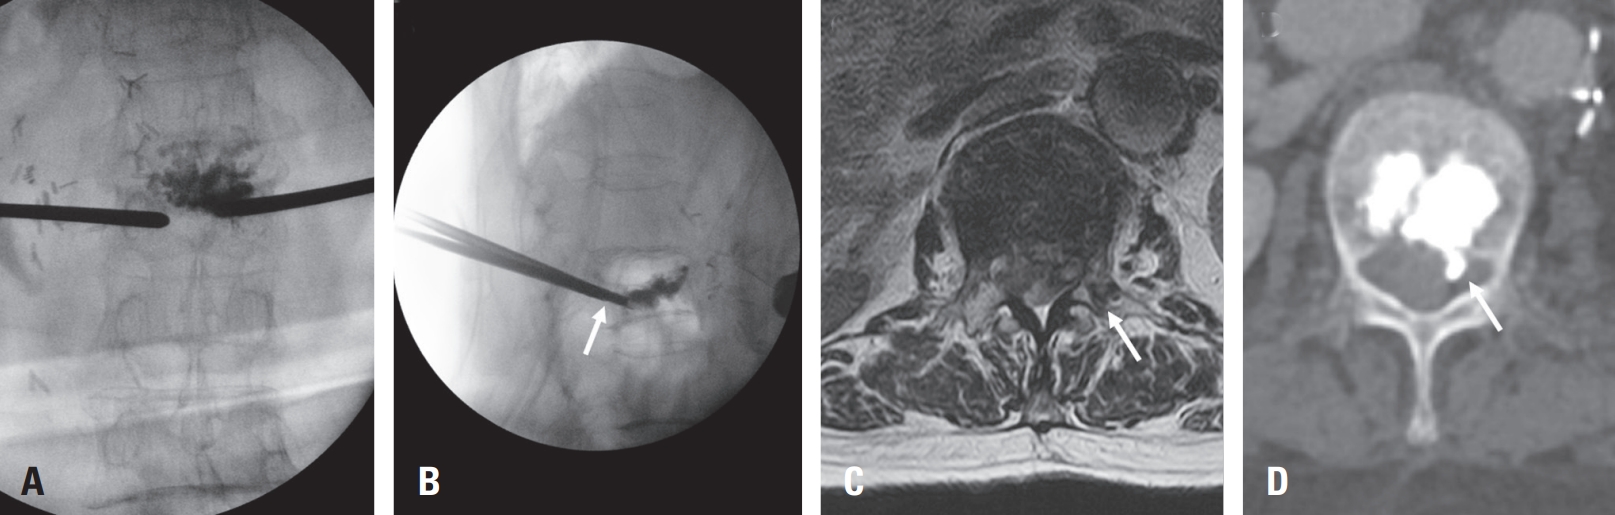

In our case, review of intraoperative fluoroscopic imaging revealed that during the left-sided needle insertion, the needle did not fully traverse the vertebral body in the lateral view, suggesting possible medial wall violation (Fig. 3A, B). Postoperative X-ray also demonstrated a very mild posterior cement leakage, which was initially overlooked due to its subtle appearance. On postoperative day 1 MRI, medial pedicle violation was suspected (Fig. 3C), and subsequent computed tomography performed after transfer to our institution demonstrated cement leakage into the spinal canal (Fig. 3D). These findings indicate that medial deviation of the needle, in combination with anticoagulation therapy (warfarin and enoxaparin), likely contributed to the development of the subdural hematoma.6,15)

Fig. 3.

Imaging suggesting medial pedicle breach and cement leakage. (A, B) Intraoperative fluoroscopic images (AP and lateral views); the needle does not fully traverse the vertebral body in the lateral view (white arrow), suggesting possible medial wall violation. (C) Postoperative day 1 MRI showing suspected medial pedicle breach (white arrow). (D) Post-transfer CT confirming cement leakage into the spinal canal (white arrow).

Fig. 3. Imaging suggesting medial pedicle breach and cement leakage. (A, B) Intraoperative fluoroscopic images (AP and lateral views); the needle does not fully traverse the vertebral body in the lateral view (white arrow), suggesting possible medial wall violation. (C) Postoperative day 1 MRI showing suspected medial pedicle breach (white arrow). (D) Post-transfer CT confirming cement leakage into the spinal canal (white arrow).